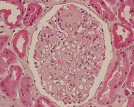

Histopatologia

Observação Macro e Microscópica de material biológico retirado por:

- Biópsias(pequenas amostras resultantes de endoscopias digestivas, colonoscopias, broncoscopias, transplantes ou de pequenas cirurgias, por exemplo retalhos de pele);

- Peças cirúrgicas(resultantes da ressecção de órgãos como vesicula biliar, útero, estómago, próstata, tumores);

Histoquímica

Técnica que, através de reações químicas, permite evidenciar determinados constituintes celulares, depósitos exógenos e microorganismos.